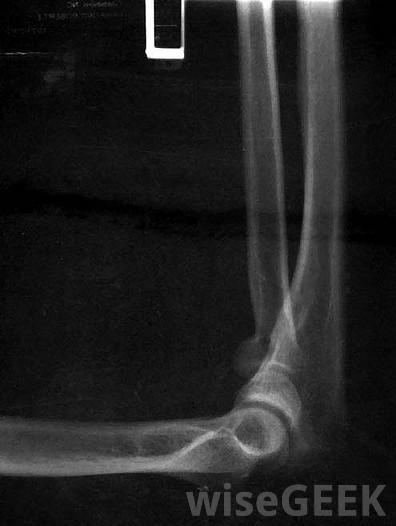

肘关节炎是肘关节的炎症一般来说,诊断肘部关节炎要看体格检查和完整的病史。体格检查可能会发现肘关节肿胀和压痛,以及发红和发热。除了体格检查外,一般情况下,在肘关节炎的情况下,x光可以显示关节变窄、身体松动或骨质疏松。偶尔,当关节炎是由损伤引起时,x光可能表明肘关节骨连接不当

肘部x光片可用于诊断肘关节炎。肘关节炎的非手术治疗通常包括活动受限,疼痛管理和物理治疗。常用的药物包括消炎药、对乙酰氨基酚和皮质类固醇有时,建议使用抑制免疫系统的药物和抗疟疾药物。物理疗法可以有效地减轻疼痛和恢复活动能力。对受影响的关节进行冷或热疗法,加上治疗性锻炼,通常可以显著恢复活动范围